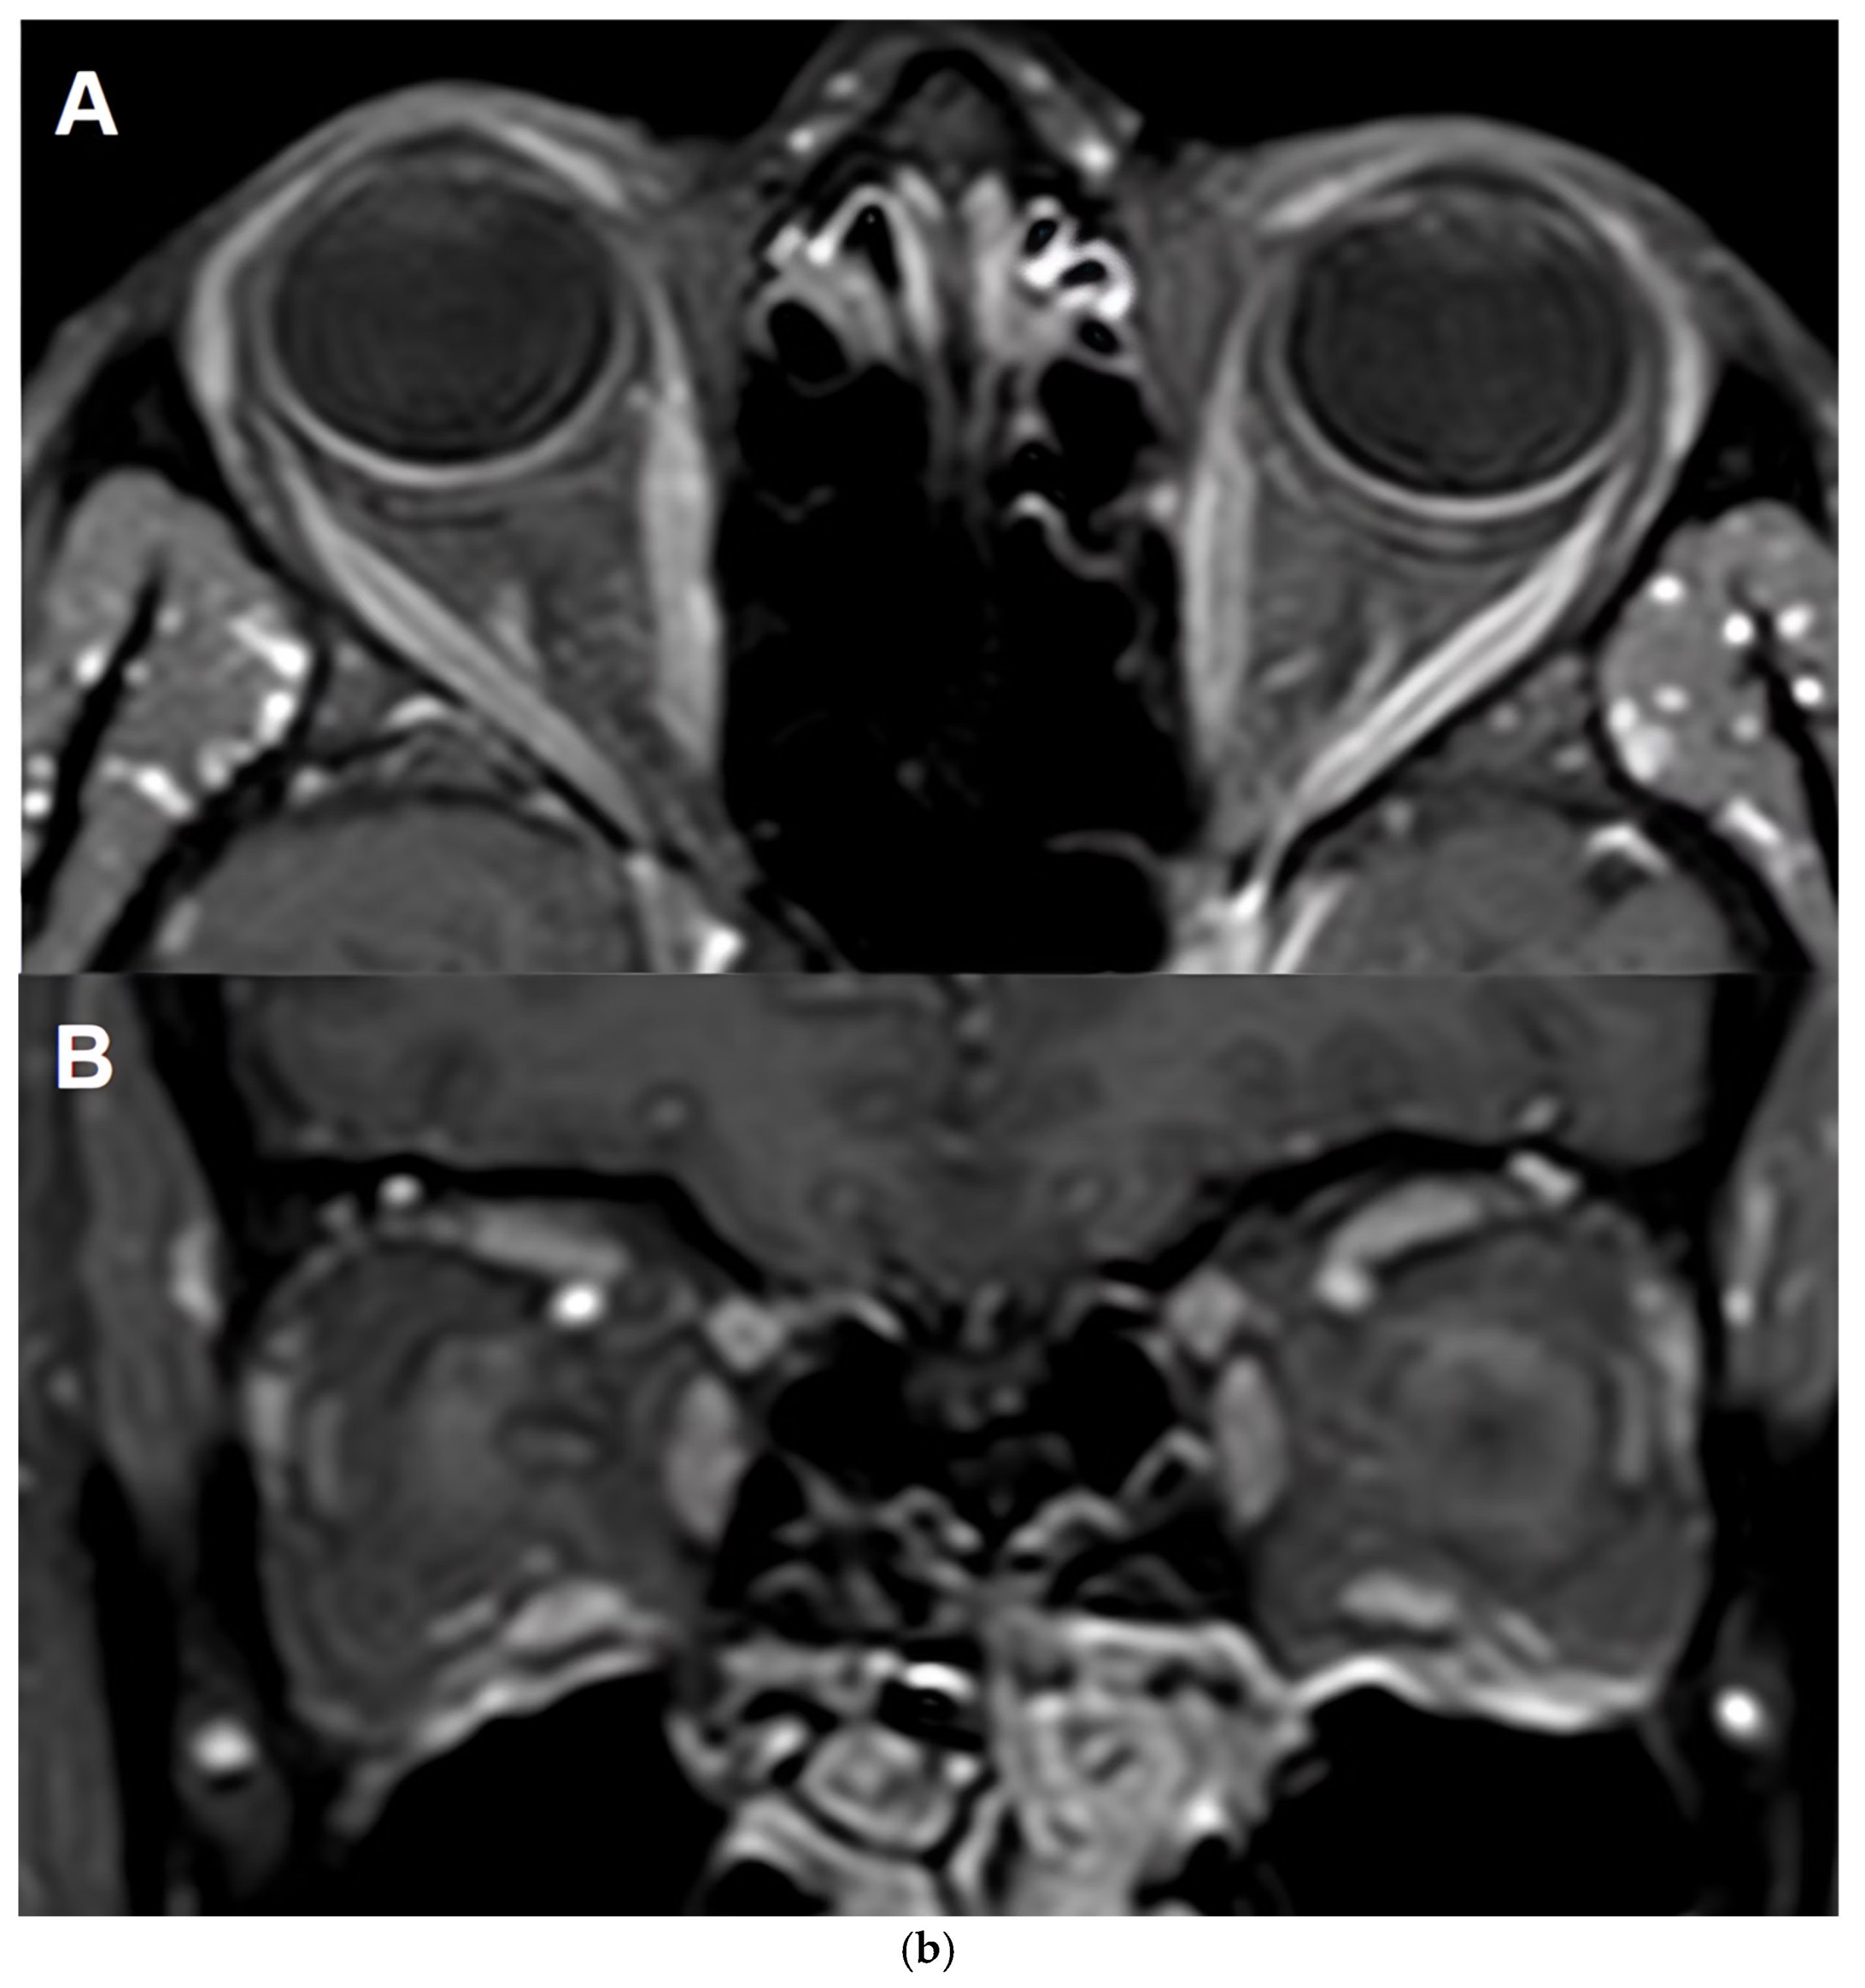

In MOGAD, ON is often bilateral and anterior compared to MS and AQP4+NMOSD, leading to pronounced acute retinal oedema followed by neuroaxonal degeneration. Unlike AQP4+NMOSD, where ON episodes are less frequent but more destructive, MOGAD patients tend to experience more frequent ON episodes with relatively better visual recovery [94,97,98]. However, repeated attacks can lead to progressive retinal thinning and visual impairment. OCT is also being investigated for its potential to detect subclinical damage and differentiate MOGAD from MS and AQP4+NMOSD based on retinal layer patterns [99,100,101]. Its accessibility and reproducibility make it a valuable tool for longitudinal monitoring in both adult and pediatric populations (Table 7).

• Neuro-Ophthalmological Features

A sub-study of 40 MOGAD patients with ON revealed that ocular pain (58%) and optic disc swelling (48%) were common. MRI and OCT findings were consistent with international MOGAD-ON patterns, including perineuritis and anterior optic nerve involvement. Interestingly, 60% of patients reported retro-orbital headache preceding visual symptoms, suggesting a potential early clinical clue. Despite severe initial visual loss, long-term outcomes were generally favourable, with a median LogMAR VA of 0.1 (20/25 Snellen equivalent) and EDSS of 1.0 at last follow-up. Nonetheless, follow-up OCT showed severe pRNFL atrophy (median 73 (range 44–95) in affected eyes [115].